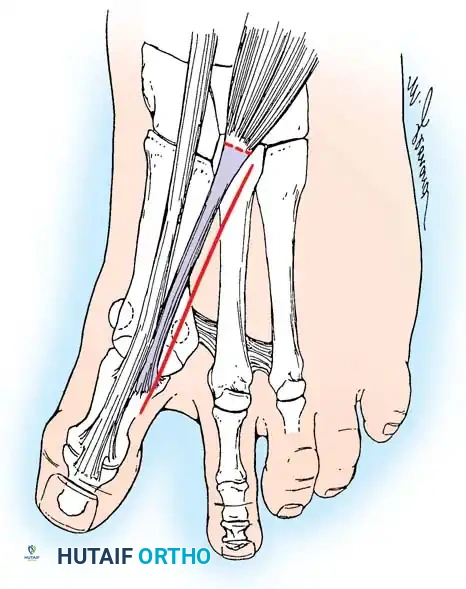

ADDUCTOR TENDON AND LATERAL CAPSULAR RELEASE

• Begin the second stage with a dorsal longitudinal incision beginning 2 to 3 mm proximal to the dorsal aspect of the fi rst web space to avoid web contracture postoperatively; extend it proximally between the fi rst and second metatarsal heads for 3 to 4 cm (Fig. 78-18). This allows adequate exposure of the adductor insertion into the base of the proximal phalanx, the lateral head of the fl exor hallucis brevis muscle converging on the fi bular sesamoid, and the entire lateral capsule from the extensor hallucis longus muscle to the plantar plate.

• The main portion of the adductor tendon inserts into the base of the proximal phalanx just plantar to the longitudinal axis of the phalanx. It also has a smaller insertion, along with the lateral head of the fl exor hallucis brevis muscle, into the fi bular sesamoid. The simplest technique to identify the insertion of the adductor hallucis tendon is to place a small, pointed, curved hemostat on the dorsolateral base of the proximal phalanx, slide it fi rmly plantarward, and lift the hemostat dorsally and laterally; the tip of the instrument usually rests in the axilla of the insertion of the adductor tendon (Fig. 78-19A). This is comparable to securing the iliopsoas tendon for tenotomy at the lesser trochanter.

• When the primary insertion is released, grasp the tendon with forceps or a hemostat, and, with traction, displace it dorsally and laterally toward the second metatarsal so that further dissection is on the medial side of the adductor or push the sesamoid sling laterally through the previously placed medial incision to aid exposure.

• While spreading the fi rst and second metatarsal heads with a small Inge retractor, heavy-duty two-tooth retractors, or a Weitlaner retractor, hold the adductor tendon under tension, which facilitates exposure. The lateral head of the fl exor hallucis brevis muscle, the lateral border of the fi bular sesamoid, and the slip of the adductor tendon (confl uent with the lateral head of the fl exor hallucis brevis muscle) come into view in the depths of the wound.

• All attachments of the adductor into its conjoined insertion with the lateral head of the fl exor hallucis brevis muscle into the fi bular sesamoid must be severed; with traction on the adductor, it freely and independently moves without tethering the fi bular sesamoid (Fig. 78-19B).

• This deep transverse intermetatarsal ligament, which lies just plantar to the adductor, may be released by the incision along the lateral border of the sesamoid. If not, release this ligament, carefully preserving the neurovascular bundle immediately beneath it, and incise the lateral capsule. Mann emphasized that release of the deep transverse metatarsal ligament endangers the neurovascular bundle to the fi rst web space, which lies immediately beneath this ligament. Sliding a small Freer elevator between this ligament and the neurovascular bundle would protect the latter structures.